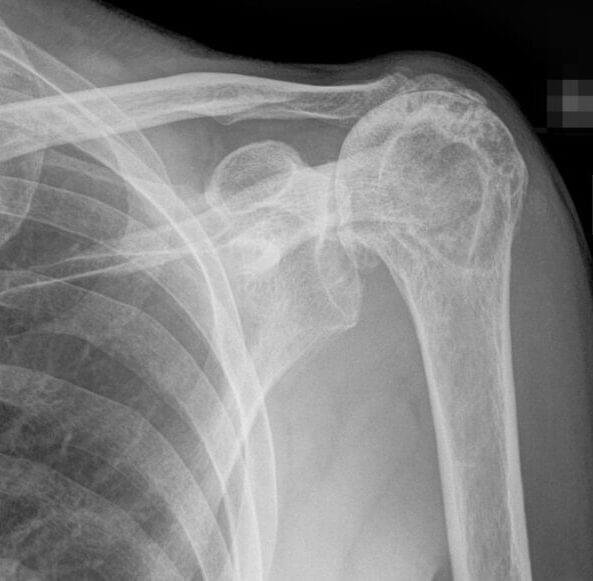

X-ray

X-ray is usually the first imaging test performed in patients with shoulder pain. Because X-rays do not show soft tissues such as the rotator cuff, findings are often normal in cases of rotator cuff injury.

The main purpose of X-ray imaging is to rule out other causes of shoulder pain, such as arthritis. In massive rotator cuff tears, the humeral head may lose stability and migrate upward toward the acromion (cranial migration), which can be clearly seen on X-ray images.